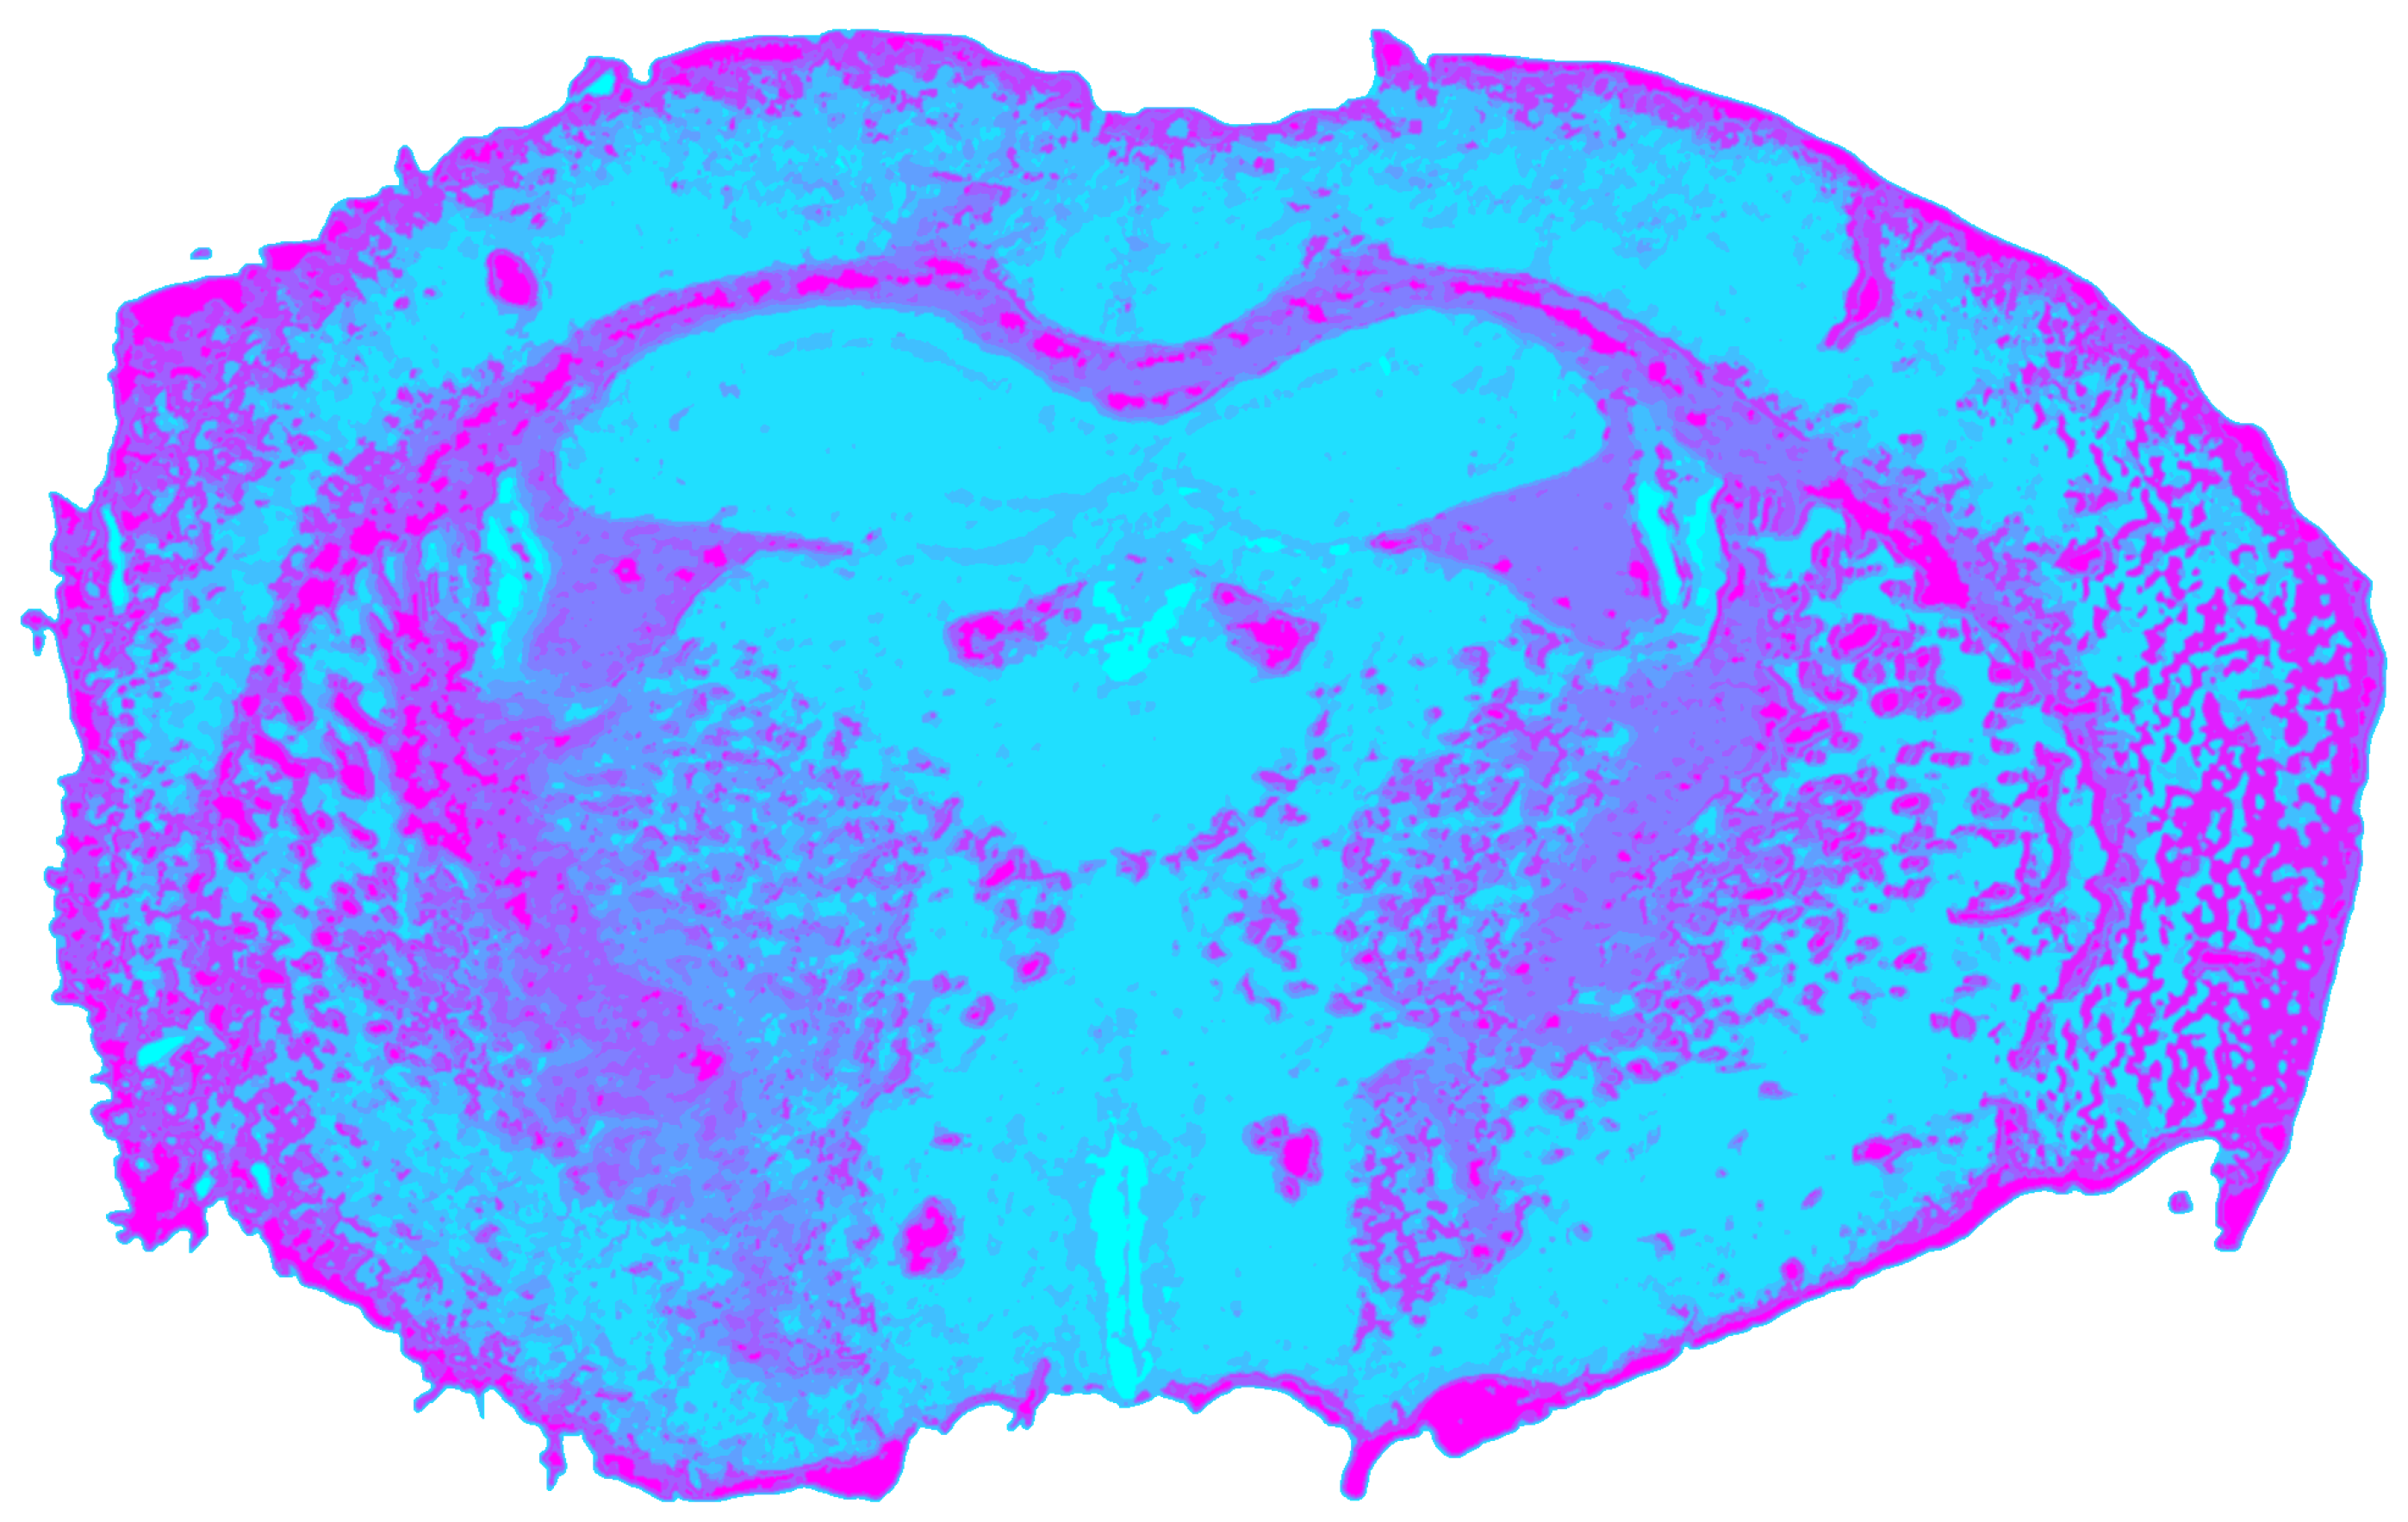

3.3. RGB Processing Results

Radiometrically normalized RGB images yielded a silhouette coefficient of sRGB = 0.6715. However, this value likely overestimates the effective segmentation quality. Although the clustering (Figure 7) reproduced major cortical boundaries and superficial differences between gray and white matter, it provided the least chemically and anatomically specific separation among all single modalities. Unlike NIR or MIR data, RGB imaging lacks molecular absorption contrast and is therefore insensitive to lipid or protein composition. Instead, its discriminative power primarily arises from structural variations in tissue architecture. Consequently, the segmentation predominantly reflects macroscopic organization rather than biochemical heterogeneity. The ventriculus lateralis was the only CSF structure that was consistently outlined, while smaller or compositionally defined regions, such as the hippocampus or hypothalamus, remained undetected.

Figure 7. Spatial clustering map of the preprocessed RGB datacube obtained with Mini-Batch KMeans (k = 9), showing the unsupervised segmentation of the mouse brain section into spectral tissue classes. Colors are consistent across figures and represent categorical cluster labels.